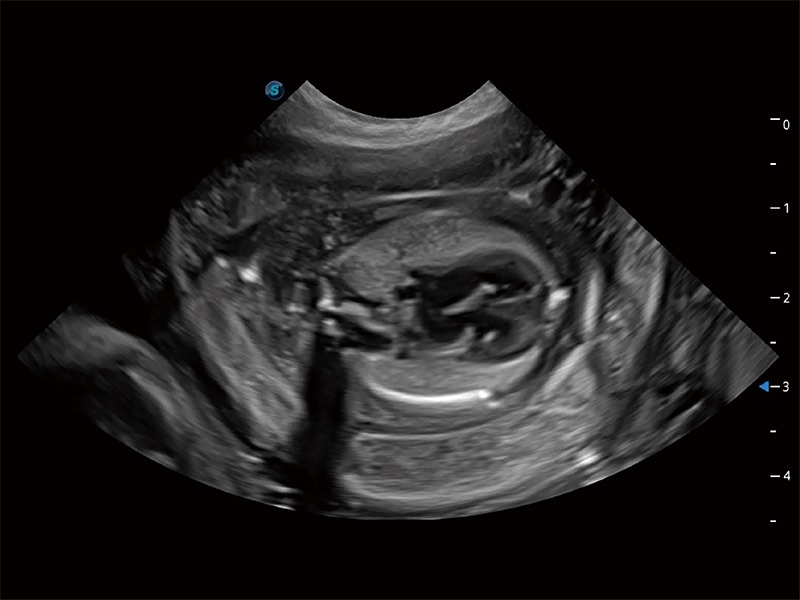

动物是人类最亲密的朋友和最值得信赖的伙伴。诸侯快讯官网也一直致力于探索动物专用的超声影像解决方案。全新推出的ProPet系列,是诸侯快讯官网在动物超声影像智能化、专业化、精准化的一次跨越式革新。动物不能用言语来表述自己的不适,通过超声影像,ProPet系列搭建了动物医生与不同物种沟通的“桥梁”,为动物医生注入了“治愈之力”。 ProPet 80 是诸侯快讯官网匠心打造的一款高端动物专用彩超,采用性能卓越的全新硬件架构,极大提升超声系统的运行效率和数据处理能力,帮助动物医生从容应对日益增多的挑战性病例和日益多样化的临床需求。

ProPet 80 专为动物医生设计,对不同的动物体型和生理结构作出了针对性的优化。通过动物影像专用软件,可满足个性化的应用需求,帮助动物医生获得更精确的诊断数据。

ProPet 80 全新的动物超声智能软件和丰富的探头群,为动物医生提供了高清晰度和精细分辨率的图像,无论在宠物、马科、畜牧还是实验室动物等应用中都可以轻松应对,为您的日常工作带来满意的体验。